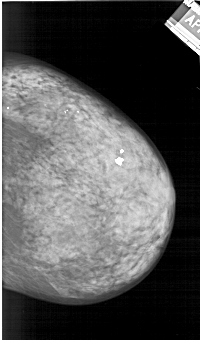

A_1242_1.RIGHT_MLO

RIGHT_CC LINES 5776 PIXELS_PER_LINE 3391 BITS_PER_PIXEL 12 RESOLUTION 43.5 NON_OVERLAY

RIGHT_MLO LINES 6181 PIXELS_PER_LINE 3766 BITS_PER_PIXEL 12 RESOLUTION 43.5 NON_OVERLAY